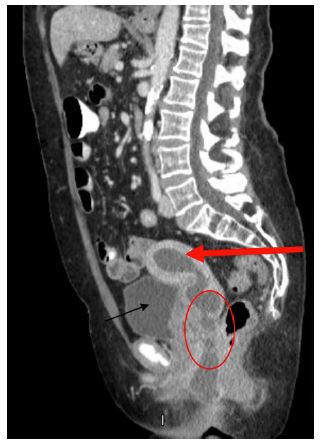

The patient represented on POD 18 again with fever and worsening perineal pain. She was febrile, white blood cell count was elevated, and CT showed a similar fluid collection in the uterus and re-accumulation of the perineal abscess (Figure 2). She was admitted for antibiotic administration and interventional radiology was consulted for drainage of the two areas of abscesses. On POD 19, a drain was placed vaginally into the uterus as well as a second drain into the perineal collection (Figures 3 & 4). The cultures ultimately revealed multidrug resistant Escherichia coli and Enterococcus raffinosus. She was subsequently treated with Meropenum. The patient improved and was discharged home on POD 27 without any further treatment necessary.

Figure 4: Drain placed within the left paravaginal portion of the abscess as shown by the thin red arrow. The drain appears bright in this image. The uterus is shown by the thick red arrow. Notice the fluid within the uterine cavity is drained after the drain placement. The bladder is shown by the thin black arrow.